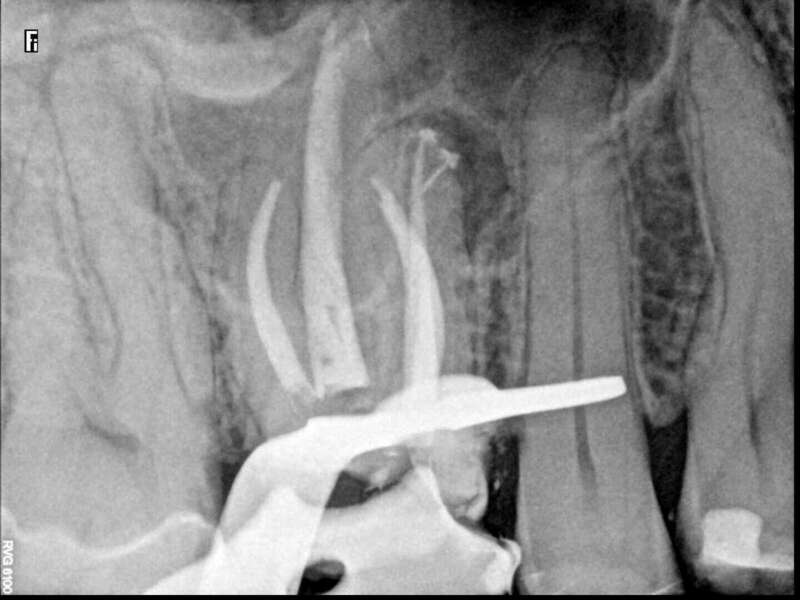

Cas du patient 4

Avant

Après